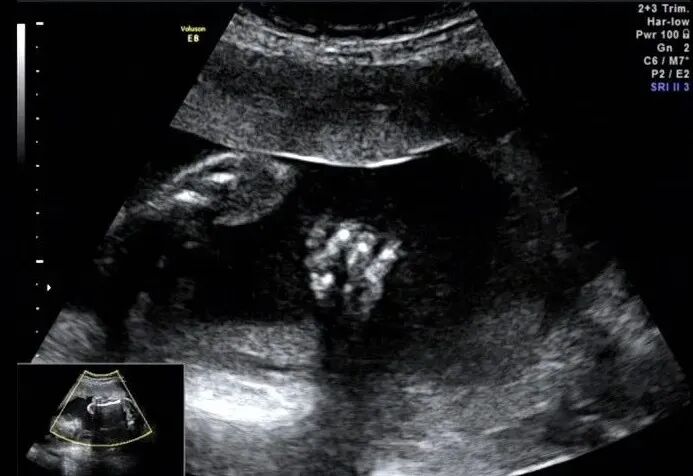

手指横断面仅显示两个,指间隙明显增大,裂隙深

再看脚也不对劲,马上启动三维超声,下图是三维超声表现

手脚都有问题,呈龙虾爪样,非常典型的手裂足裂,胎儿父母没有啥疾病